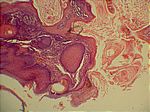

Keratoakanthom, HE